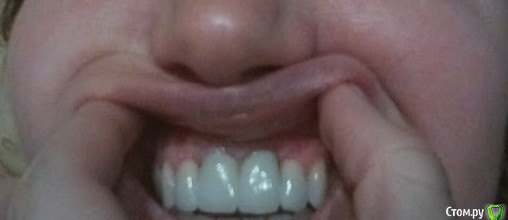

red_butler Опубликовано 20 ноября, 2016 Поделиться Опубликовано 20 ноября, 2016 Покажите фото во рту, что бы было видно десну Ссылка на комментарий

ЕленаR Опубликовано 20 ноября, 2016 Автор Поделиться Опубликовано 20 ноября, 2016 Не пугайтесь Ссылка на комментарий

Jurai Опубликовано 20 ноября, 2016 Поделиться Опубликовано 20 ноября, 2016 нас таким не испугать) чуть шире бы снимок, посмотреть положение имплантатов относительно зубов. В идеале - КТ.Ситуация неприятная, но не безнадежная. Ссылка на комментарий